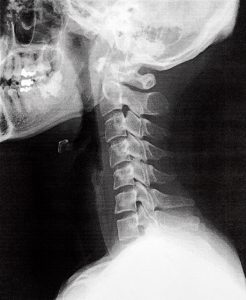

ご存知の通り、ヒトの首=頚椎は7個の骨で構成されており、前弯という形状が生理的≒自然な形、理想と言われております。

7個の頸椎は、頭のサポートと運動のために最適な数とされており、前弯により頭部の重量を分散し、首への負担を軽減するそうです。

ストレートネックは、頸部の筋肉や靭帯に不必要な圧力をかける、頚椎や周辺組織にこれにより、慢性的な首の痛みや不快感が起こる。